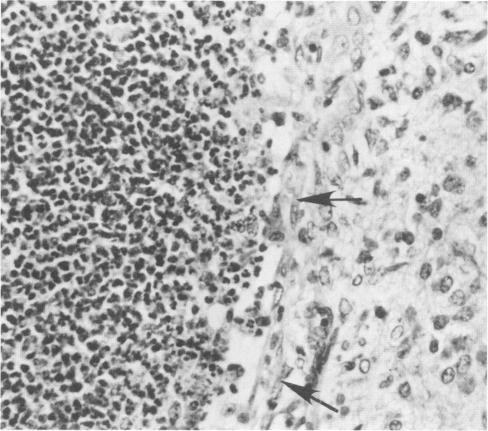

Citrobacter diversus is a cause of devastating neonatal meningitis, with illness characterized by formation of multiple brain abscesses. We developed an infant mouse intracranial inoculation model to evaluate the pathophysiology of C. diversus neonatal infections. Eighteen of 26 strains inoculated intracranially at a dose of ca. 3.3 x 10(3) CFU caused greater than 50% mortality in 2-day-old mice. No correlation was seen between the epidemiologic characteristics of a strain and its rate of mortality. When seven C. diversus isolates (four isolates from patients with meningitis, three from non-central nervous system [CNS] sites) were further evaluated, mortality was significantly correlated with bacteremia. The initial lesion in the CNS was a suppurative ventriculitis beginning 1 to 2 days postinoculation. Subsequent ventriculomegaly was associated with ventriculitis and periventricular abscessation. Brain lesions were seen with all strains, although strains of low virulence (as measured by having no bacteremia and low mortality) caused less-severe damage. An age-related susceptibility to C. diversus brain lesions was demonstrated, with 5-day-old mice showing a significant reduction in, and 8-day-old mice being apparently resistant to, infection and CNS damage. Our data indicate that C. diversus has a propensity to cause abscess formation in the neonatal mouse brain, with characteristic pathologic findings; however, the factors that determine whether a strain will cause meningitis in a human infant remain to be identified.

奇异柠檬酸杆菌是导致新生儿毁灭性脑膜炎的病因,其病症特征为形成多个脑脓肿。我们建立了一种幼鼠颅内接种模型,以评估奇异柠檬酸杆菌新生儿感染的病理生理学。以约3.3×10³CFU的剂量颅内接种26株菌株,其中18株在2日龄小鼠中导致了超过50%的死亡率。菌株的流行病学特征与其死亡率之间未发现相关性。当对7株奇异柠檬酸杆菌分离株(4株来自脑膜炎患者,3株来自非中枢神经系统[CNS]部位)进行进一步评估时,死亡率与菌血症显著相关。中枢神经系统的初始病变是接种后1至2天开始的化脓性脑室炎。随后的脑室扩大与脑室炎和脑室周围脓肿形成有关。所有菌株均可见脑损伤,尽管低毒力菌株(通过无菌血症和低死亡率衡量)造成的损伤较轻。研究表明幼鼠对奇异柠檬酸杆菌脑损伤存在年龄相关易感性,5日龄小鼠感染和中枢神经系统损伤明显减少,8日龄小鼠对感染和中枢神经系统损伤明显具有抵抗力。我们的数据表明,奇异柠檬酸杆菌易于在新生小鼠脑内形成脓肿,具有特征性病理表现;然而,决定菌株是否会在人类婴儿中引起脑膜炎的因素仍有待确定。